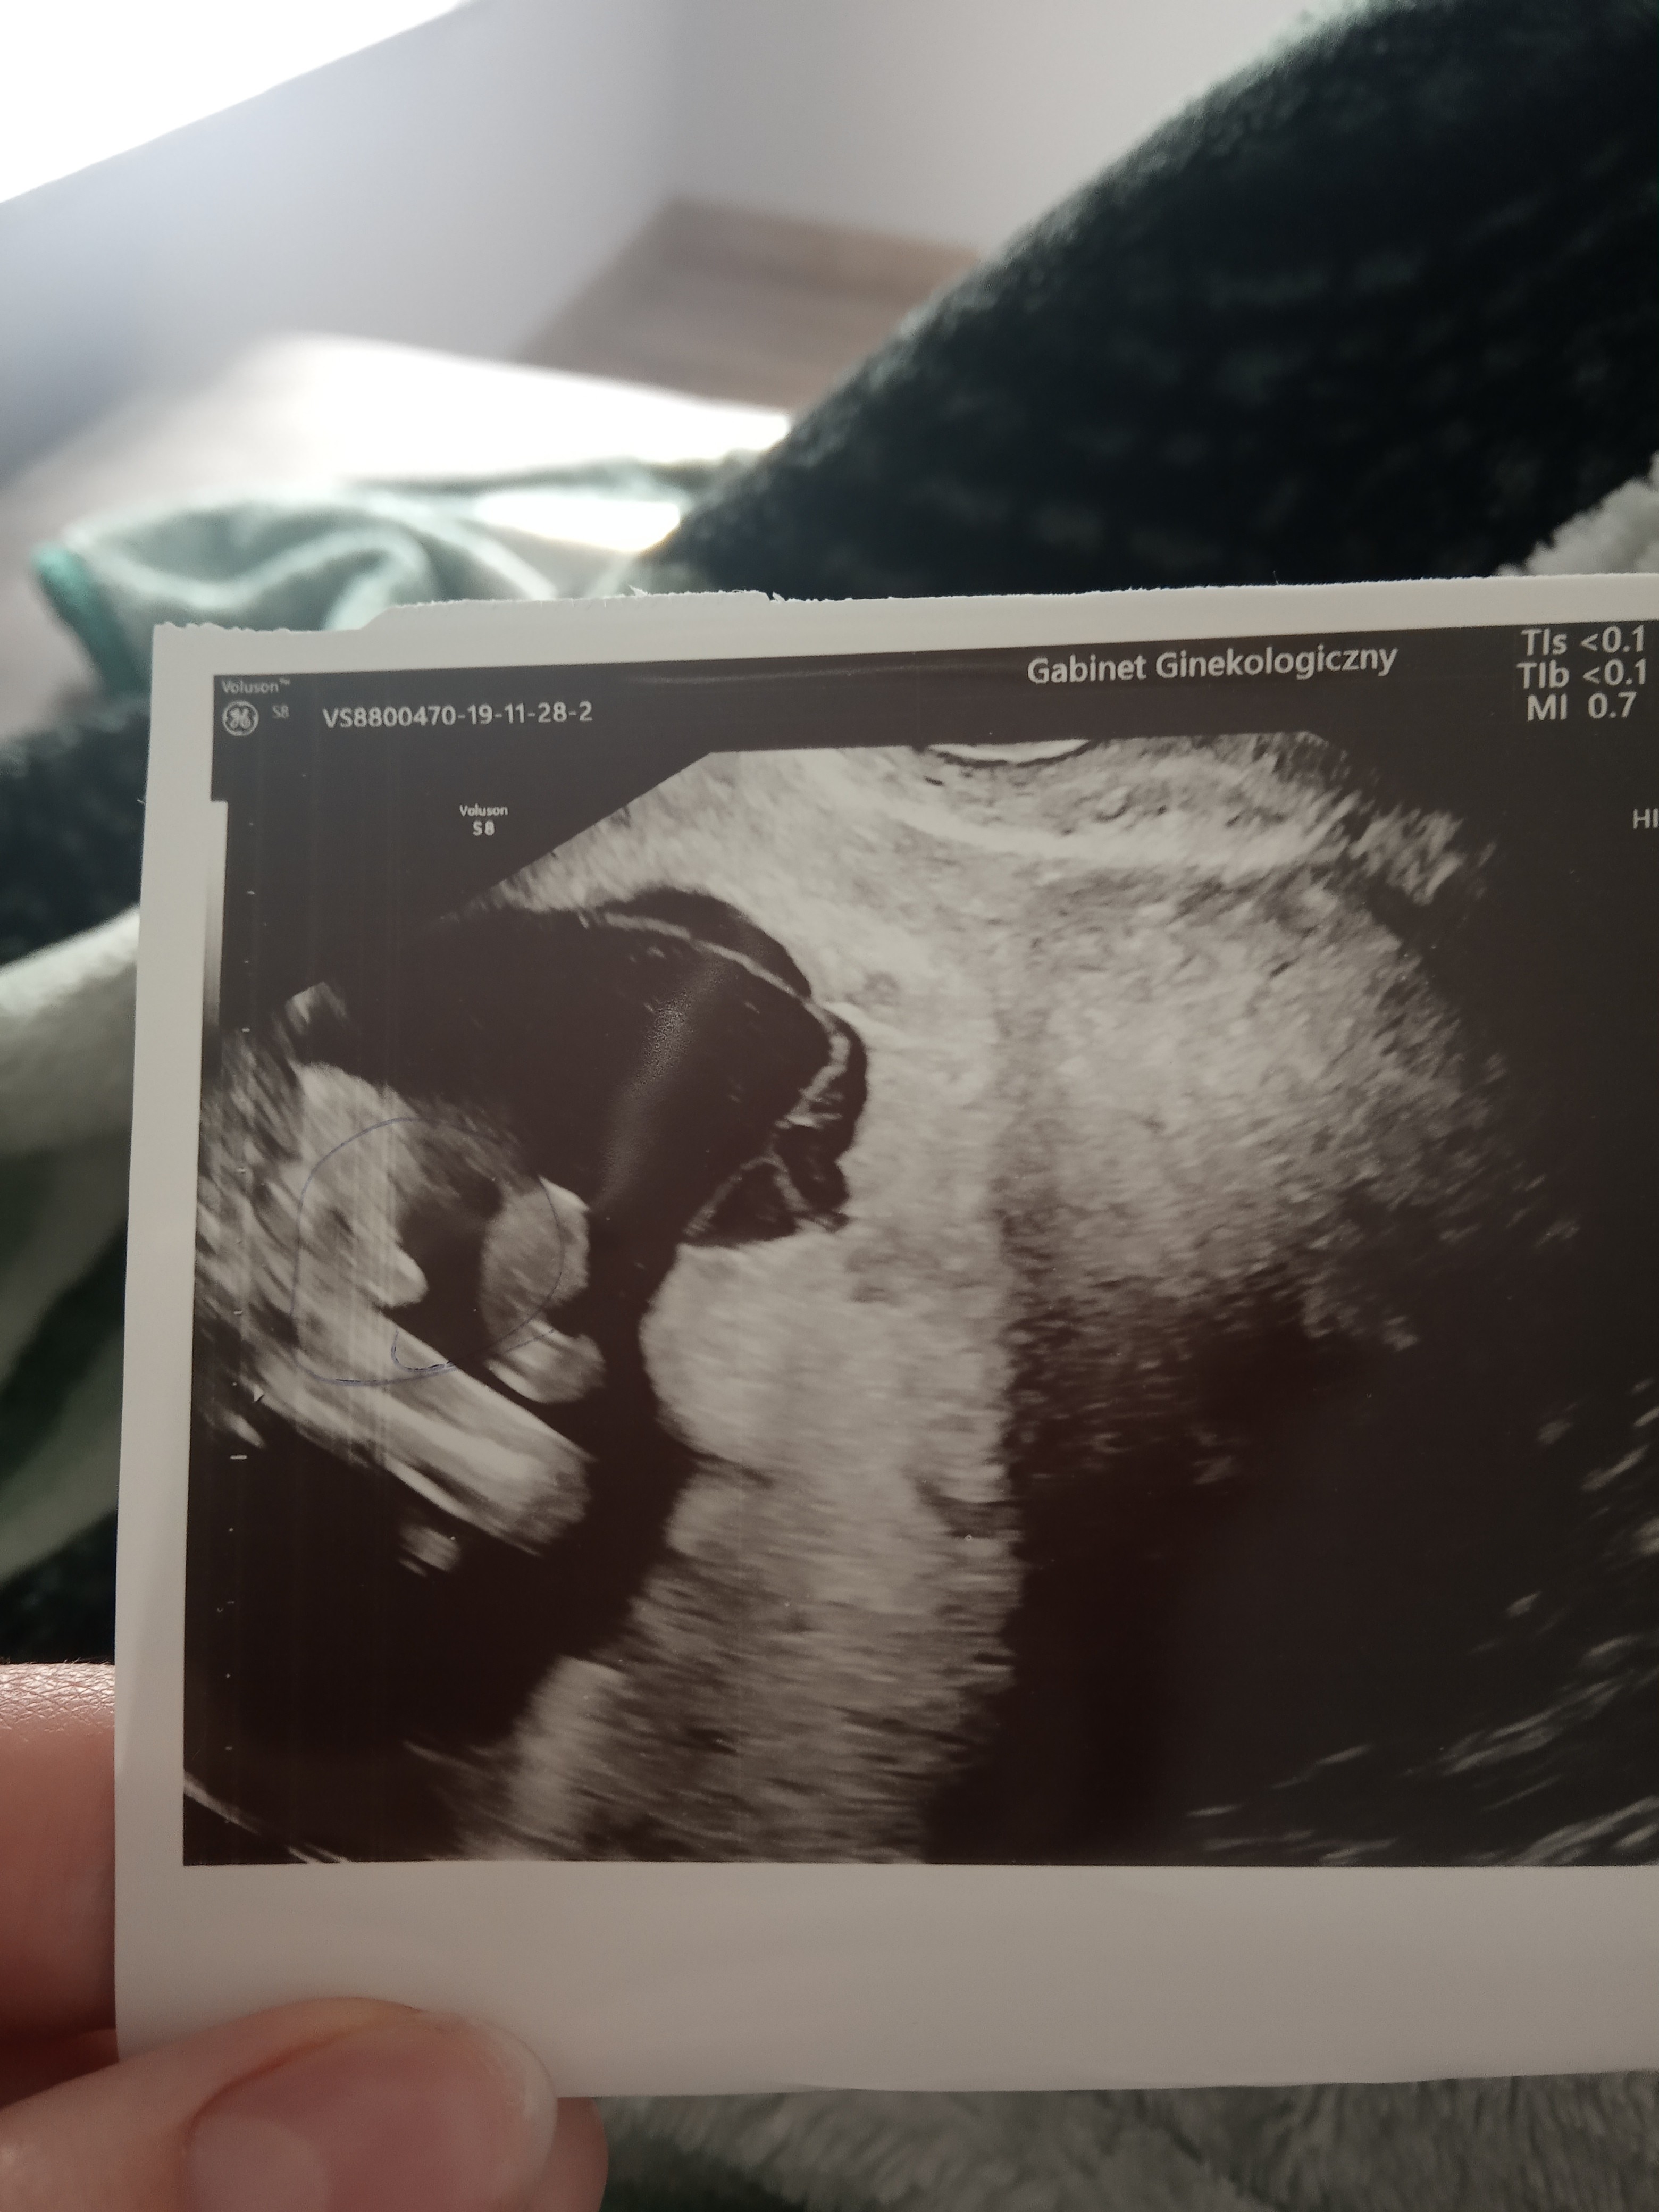

Usg chłopak czy dziewczynka

Witam w 19 tygodniu ciąży dowiedziałam się ze będę miała dziewczynkę w 20 tyg okazało się jednak , że to chłopak. Sama już nie wiem bo na jednym usg widać na pewno dziewuche a na drugim chłopca. Może to pempowina ?? Może ktoś mi pomoże rozwiązać ta zagadkę

Cześć dziewczyny proszę was o ocenę zdjęcia usg... Miesiąc temu zapowiedzieli mi syna a 4 grudnia na połówkowym ze córka... Trochę mam mętlik w głowie 😞

Wyrostek twojego dziecka mógłby byc dziewczynkowy, gdyby nie ta gruba kropa nad nim... co właśnie przeważyło szale opinii. Chyba ze akurat jest to część czegoś innego.

lekarka nie jest pewna sugeruje chłopca po usg ale rak nie da uciąć